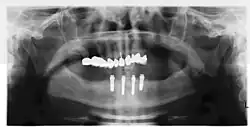

Рентген четырёх имплантатов Штраумана и абатментов